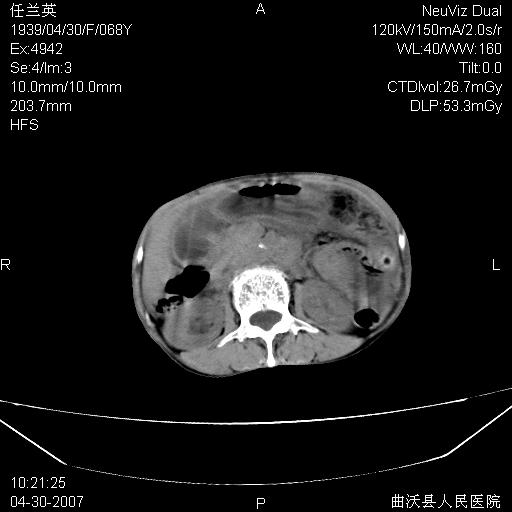

患者,女,68岁,感觉腹部憋涨发硬数天,查b超发现左盆腔有囊性肿物和少量腹水,行ct检查

1.考虑卵巢肿瘤并腹腔广泛性转移可能性大;

2.腹盆腔少量积液。

支持左侧卵巢恶性肿瘤伴网膜、腹膜广泛转移。

难的一见 典型 - 网膜饼  冰冻骨盆 可以当教学片了